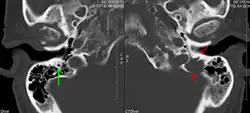

Medical imaging

The diagnostic examination of a person with suspected multiple myeloma typically includes a skeletal survey. This is a series of X-rays of the skull, axial skeleton, and proximal long bones. Myeloma activity sometimes appears as "lytic lesions" (with local disappearance of normal bone due to resorption) or as "punched-out lesions" on the skull X-ray ("raindrop skull"). Lesions may also be sclerotic, which is seen as radiodense.[76] Overall, the radiodensity of myeloma is between −30 and 120 Hounsfield units (HU).[77] Magnetic resonance imaging is more sensitive than simple X-rays in the detection of lytic lesions. An MRI may supersede a skeletal survey, especially when vertebral disease is suspected. Occasionally, a CT scan is performed to measure the size of soft-tissue plasmacytomas. Nuclear Medicine Bone scans are typically not of any additional value in the workup of people with myeloma (no new bone formation; lytic lesions not well visualized on nuclear bone scan).

Pathological fracture of the lumbar spine due to multiple myeloma -

A CT of the brain revealed a lytic lesion in the left temporal bone (right side of image), and petrous temporal bones involving the mastoid segment of the facial nerve canal. Red arrows: lesion; green arrow: normal contralateral facial nerve canal. The lesions are consistent with a myeloma deposit.